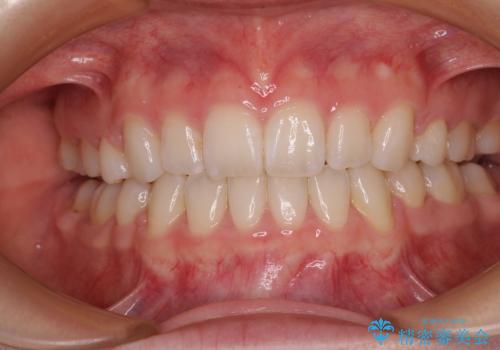

4本の歯を抜歯したことで、飛び出していた口元が引っ込み、横顔が大きく改善されました。